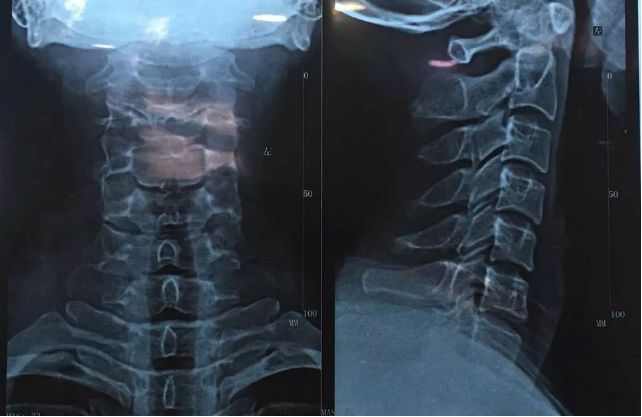

颈椎可不是简单的堆砌,它可是有自己标准姿势——前凸后凹的“C”字型,这样的结构能起到很好的缓冲作用,加上颈椎周围还有很多肌肉帮忙支撑,所以颈椎撑起重重的头颅还能那么活跃。

颈椎生理曲度改变

长时间受到牵拉的肌肉,其肌纤维断裂而削弱原本的功能而造成颈椎不平衡,还会使颈椎失去正常的“C”型结构,如变直,即“颈椎生理曲度变直”,严重者表现为前凹后凸的“反C”字形,也就是我们常说的“颈椎反弓”。